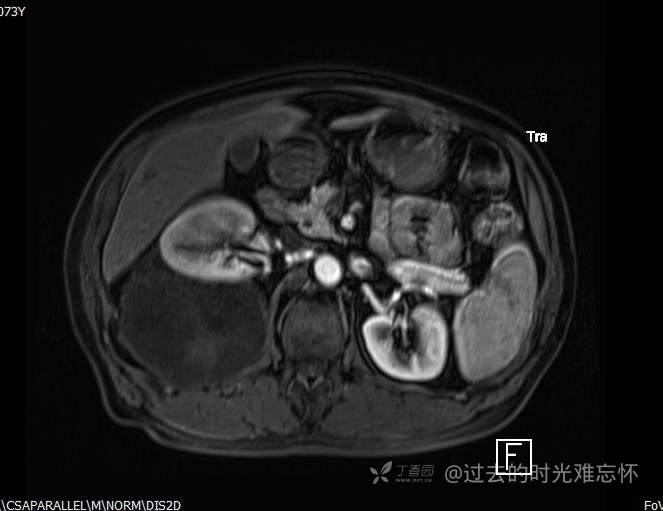

患者性别:男

患者年龄:73岁

主诉:咳嗽1月余。曾有血尿一次。后背部酸痛不适1-2年左右,无明显消瘦。

辅助检查:CT MRI

临床诊断:占位

治疗经过:手术

增强